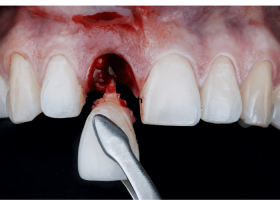

Mới Nhổ Răng Có Nên Ngậm Nước Muối? - Hướng Dẫn Toàn Diện Từ Chuyên Gia Răng Hàm Mặt

Đăng lúc: 16-05-2025Hướng dẫn đầy đủ về thời điểm và cách sử dụng nước muối sau nhổ răng, giải đáp thắc mắc phổ biến, và các lưu ý chăm sóc vết thương hậu phẫu từ...

Nhổ Răng Xong Nên Làm Gì? Chăm Sóc Đúng Cách | Bs Cường

Đăng lúc: 16-05-2025Sau khi nhổ răng xong nên làm gì để giảm đau, nhanh lành và tránh biến chứng là thắc mắc của rất nhiều người. Đọc ngay hướng dẫn chi tiết từ Bác sĩ Cường...